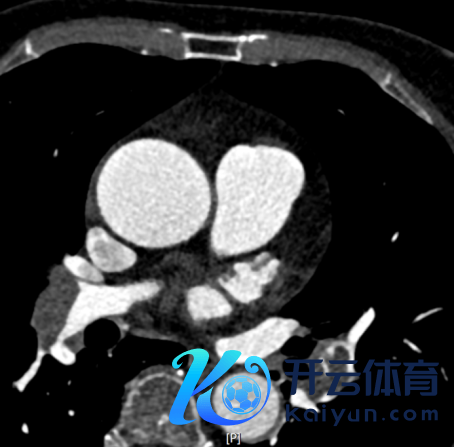

强化CT扫描刚完结,CT见“双肺动脉、双侧各叶段动脉内见多发条片状低密度充盈缺损,冠状动脉前降支局限性非钙化斑块,管腔轻微褊狭”(图3-5)。

图5.CTPA成果